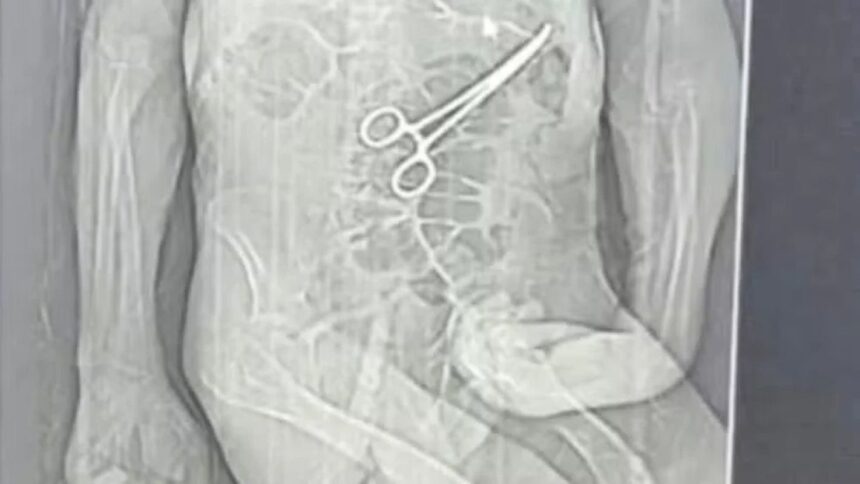

Após a morte, a família teve conhecimento de uma tomografia divulgada por uma rádio local que indicaria a presença de uma pinça cirúrgica dentro do corpo do paciente. Segundo o advogado dos familiares, Iuri Evangelista Furtado, a partir desse exame começaram a ser adotadas medidas legais.

Durante a internação, o idoso apresentou dores e sonolência excessiva, o que chamou a atenção da cuidadora contratada pela família. No dia 11 de dezembro, após suspeita de um AVC, foi realizada uma tomografia. De acordo com o boletim de ocorrência, pouco depois do exame Manoel foi levado às pressas para uma segunda cirurgia, sem que os familiares fossem informados sobre o motivo.